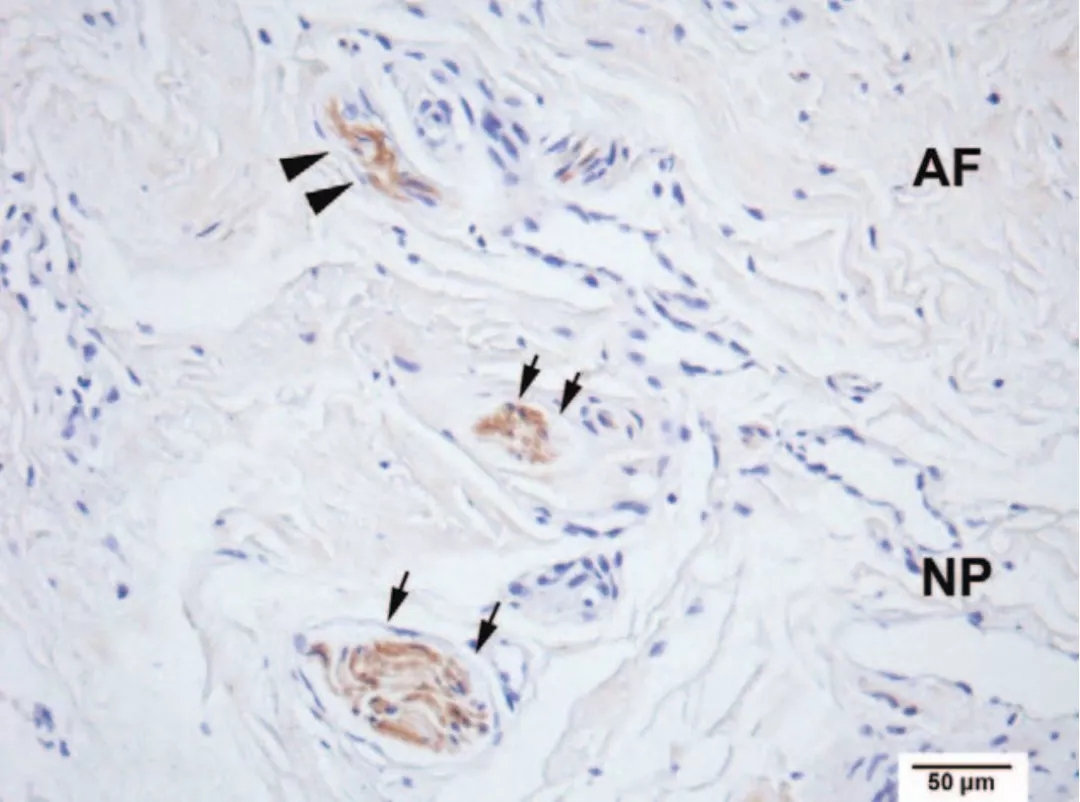

权威脊柱外科杂志《SPIINE》报道,有专家发现,在颈椎病眩晕患者的椎间盘内,有一种特殊的物质,叫鲁菲尼小体。它在正常的椎间盘中是没有的或者仅仅在椎间盘最外层有少量分布。那么,颈椎病眩晕是否和鲁菲尼小体有关呢?

当出现颈椎病,存在椎间盘病变时,椎间盘内的鲁菲尼小体便会异常增生或长入。这样,鲁菲尼小体在椎间盘内由于炎症的刺激发生“敏化”,最后它传出的信号是异常的本体感受信号,会产生感觉错配,出现眩晕。